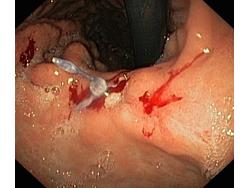

Krwawienie